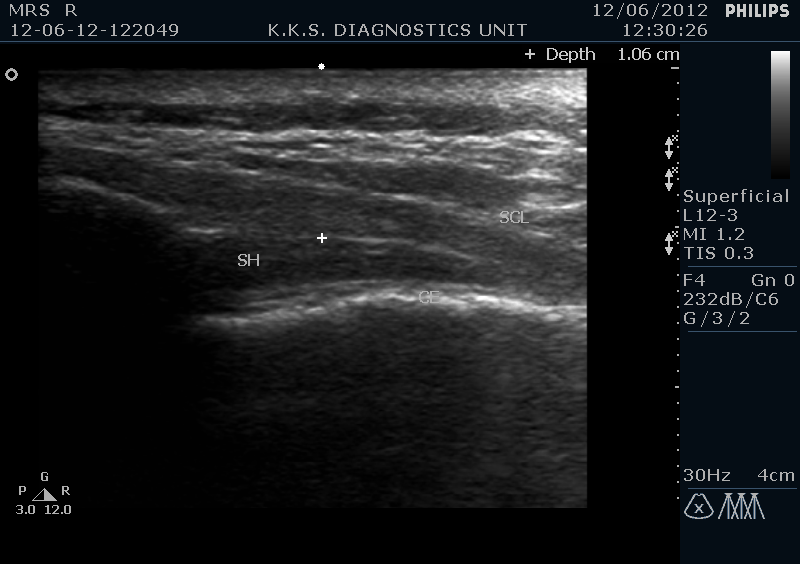

In prone position the scanning is initiated from midline in transverse probe alignment from the median crest of the sacrum which is seen as an echogenic bony prominence .As we proceed caudad from this level we encounter in para-sagittal region bilaterally two convex echogenic shadows with a hypo echoic 2-3mm band running between the two. These are the saccral cornua with saccral hiatus in between . Superior to this configuration, is a hypoechoic band of saccrococcygeal ligament and posteriorly a dense echogenic line of posterior surface of the sacral bone.

In the longitudinal view, sacral hiatus is seen as a darkish hypoechoic beak like structure which is enclosed between the sacrococcygeal ligament superiorly and sacral bone inferiorly.

Sonograhic Long. View sacral hiatus Tr. View sacral hiatus with sacral cornu

Ultrasound probe with frequency range between 12-7 MHz is placed transversely at the level of the sacral dip in midline for the location of the sacral hiatus. Sacral cornu are sonographically important landmarks and the space of few millimeters between the two, seen transversely as hypoechoic region, is the sacral hiatus.

At this level the transducer is then rotated longitudinally and the relatively echogenic band superior to the is hiatus is the sacrococcygeal ligament and the inferior echogenic line is formed by the posterior cortical surface of the sacral bone.